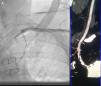

Figure 1.

(A) Sub-occlusive stenosis of left subclavian artery on angiogram. (B) CT angiography of supra-aortic vessels shows sub-occlusive and calcified stenosis of the subclavian artery ostium with heavy calcification of the aorta.